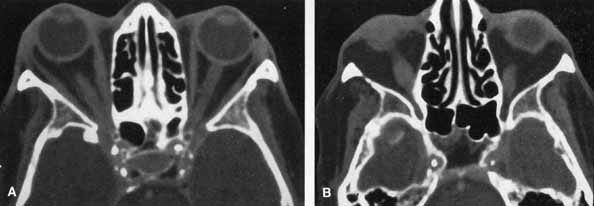

ORBIT.

HZO orbital myositis resulting proptosis and extraocular muscle palsies has been described.82 HZO can produce ptosis from a secondary Horner's syndrome. Kattah and Kennerdell83 reported on two patients with orbital apex syndrome (optic neuropathy with complete ophthalmoplegia and anesthesia), associated with meningoencephalitis. A patient with HZO with proptosis, optic neuropathy, and restriction of abduction and up-gaze showed marked enlargement of the inferior and medial rectus muscles on computed tomography (CT) scanning, which resolved with systemic corticosteroid therapy (Fig. 19A and 19B).84 Orbital myositis is a cause of HZO-associated ophthalmoplegia, an entity most often attributed to primary or secondary cranial nerve VZV involvement.

Fig. 19 Orbital myositis in herpes zoster ophthalmicus (HZO). Axial contrasted orbital computed tomographic scan, demonstrating enlargement of right medial rectus (A) and right inferior rectus (B) muscles.